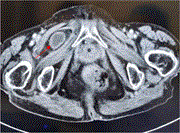

Mixed primary and secondary vaginal calculi: a case report

Ghassan Alhajress and others

Journal of Surgical Case Reports, Volume 2023, Issue 10, October 2023, rjad486, https://doi.org/10.1093/jscr/rjad486